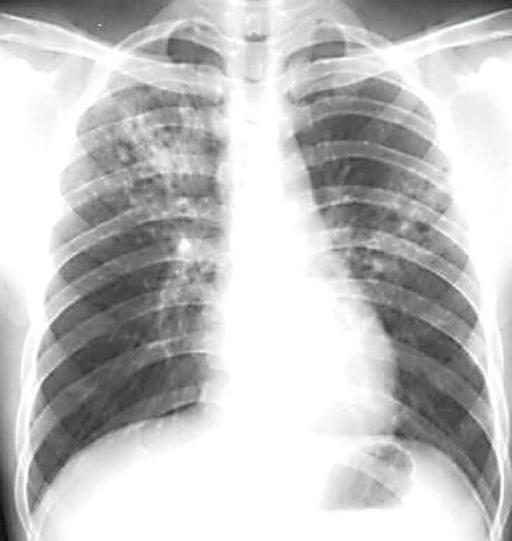

结核病俗称“痨病”,是由结核分枝杆菌感染引起的一种传染性疾病,几乎人体所有组织、器官均可发生,其中肺结核最为常见。

由于不是所有感染者均出现症状,有些人会在偶然的胸片或胸部CT检查时发现可疑肺结核病灶。这时需要进一步完善检查来明确这些病灶是否由结核杆菌感染引起,如痰涂片后显微镜下找结核杆菌、痰结核菌培养、痰结核杆菌核酸检测、组织活检病理学检查、支气管镜检查,以及结核菌素试验、γ-干扰素释放试验等免疫学检查,但免疫学检查只能告诉你是否感染过结核杆菌,而不能明确目前是否处于结核活动期。还有些患者是因发现胸水就诊的,胸水的化验和检查有助于结核性胸膜炎的诊断。